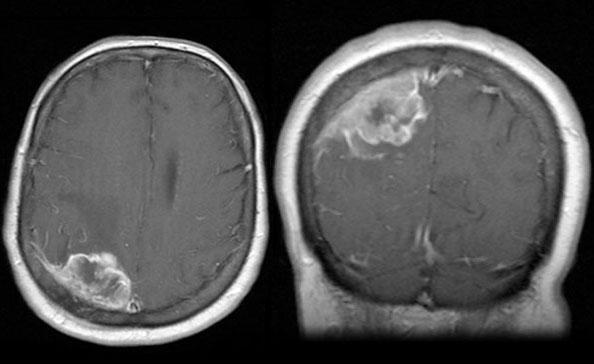

三级脑膜瘤能治愈吗?首先,来认识一下脑膜瘤这种脑瘤。脑膜瘤是比较常见的原发性脑瘤类型,约占全部脑瘤的30%。它起源于脑膜,即位于颅骨和大脑之间的三层保护组织。

3级(恶性或间变性):这种侵袭性的脑肿瘤倾向于侵入比较靠近肿瘤的大脑部分。大约1%至4%的脑膜瘤为III级(癌性)。

三级脑膜瘤包括哪几种?三级脑膜瘤通常包括乳头状、横纹肌样和间变性肿瘤。通常复发率高,并可能转移到颅外部位。间变性脑膜瘤的预后较差,中位总体生存期(OS)小于1年。